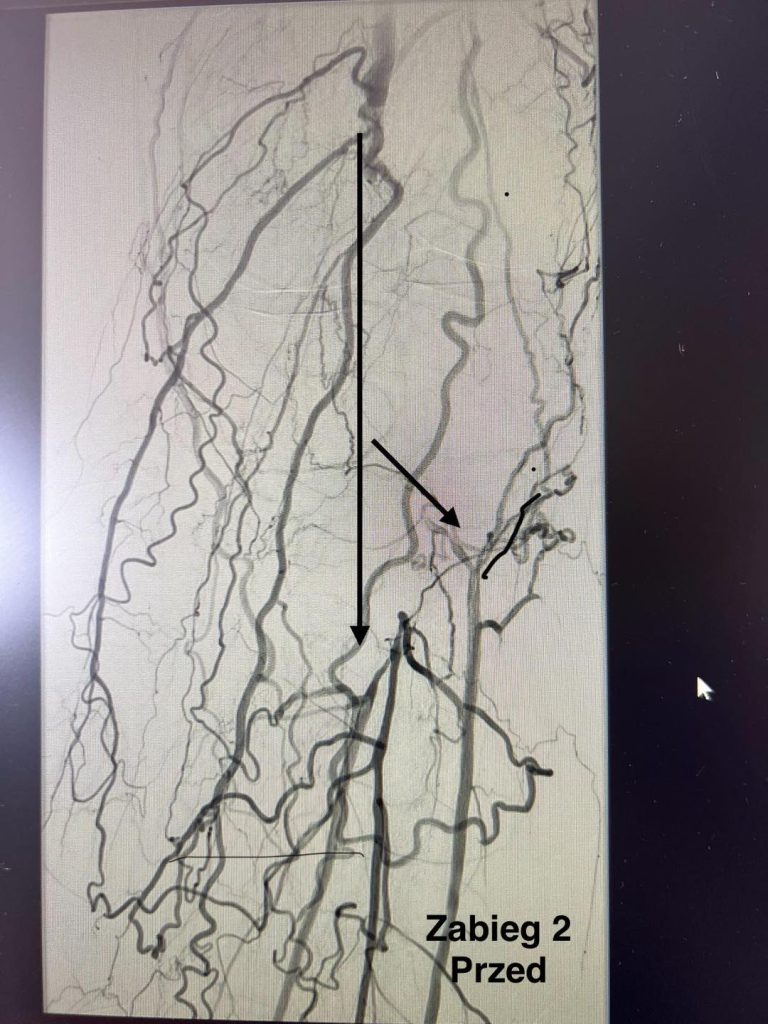

Drugi zabieg przeprowadzono u pacjenta z cukrzycą i przewlekłym niedokrwieniem kończy dolnej. Po amputacji palca u stopy rana nie goiła się prawidłowo. W czasie zabiegu udrożniono tętnicę podkolanową i tętnice podudzia, co poprawiło krążenie. Stan pacjenta po zabiegu był dobry, został wypisany do domu.